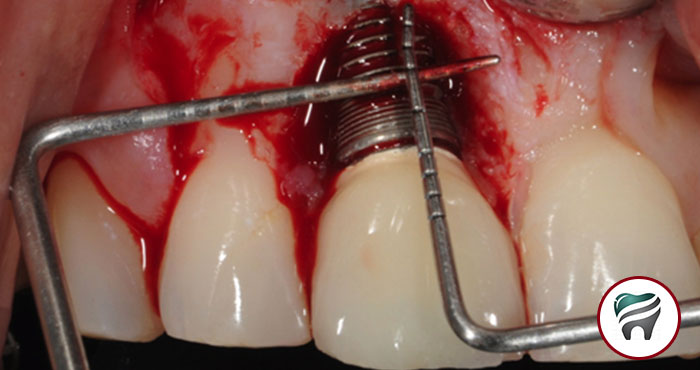

Peri-implantite é uma perda óssea progressiva ao redor dos implantes, já osseointegrados, com formação de bolsa acompanhada ou não de sangramento e/ou supuração. Clinicamente, a Peri-implantite é caracterizada por inflamação dos tecidos, hemorragia e perda de osso junto ao implante, levando muitas vezes à exposição do implante dentário.

O termo Peri-implantite é usado em razão das semelhanças clinicas, histológicas emicrobiológicas com a periodontite. A evolução deste quadro clínico leva, em último caso, à perda do implante dentário.